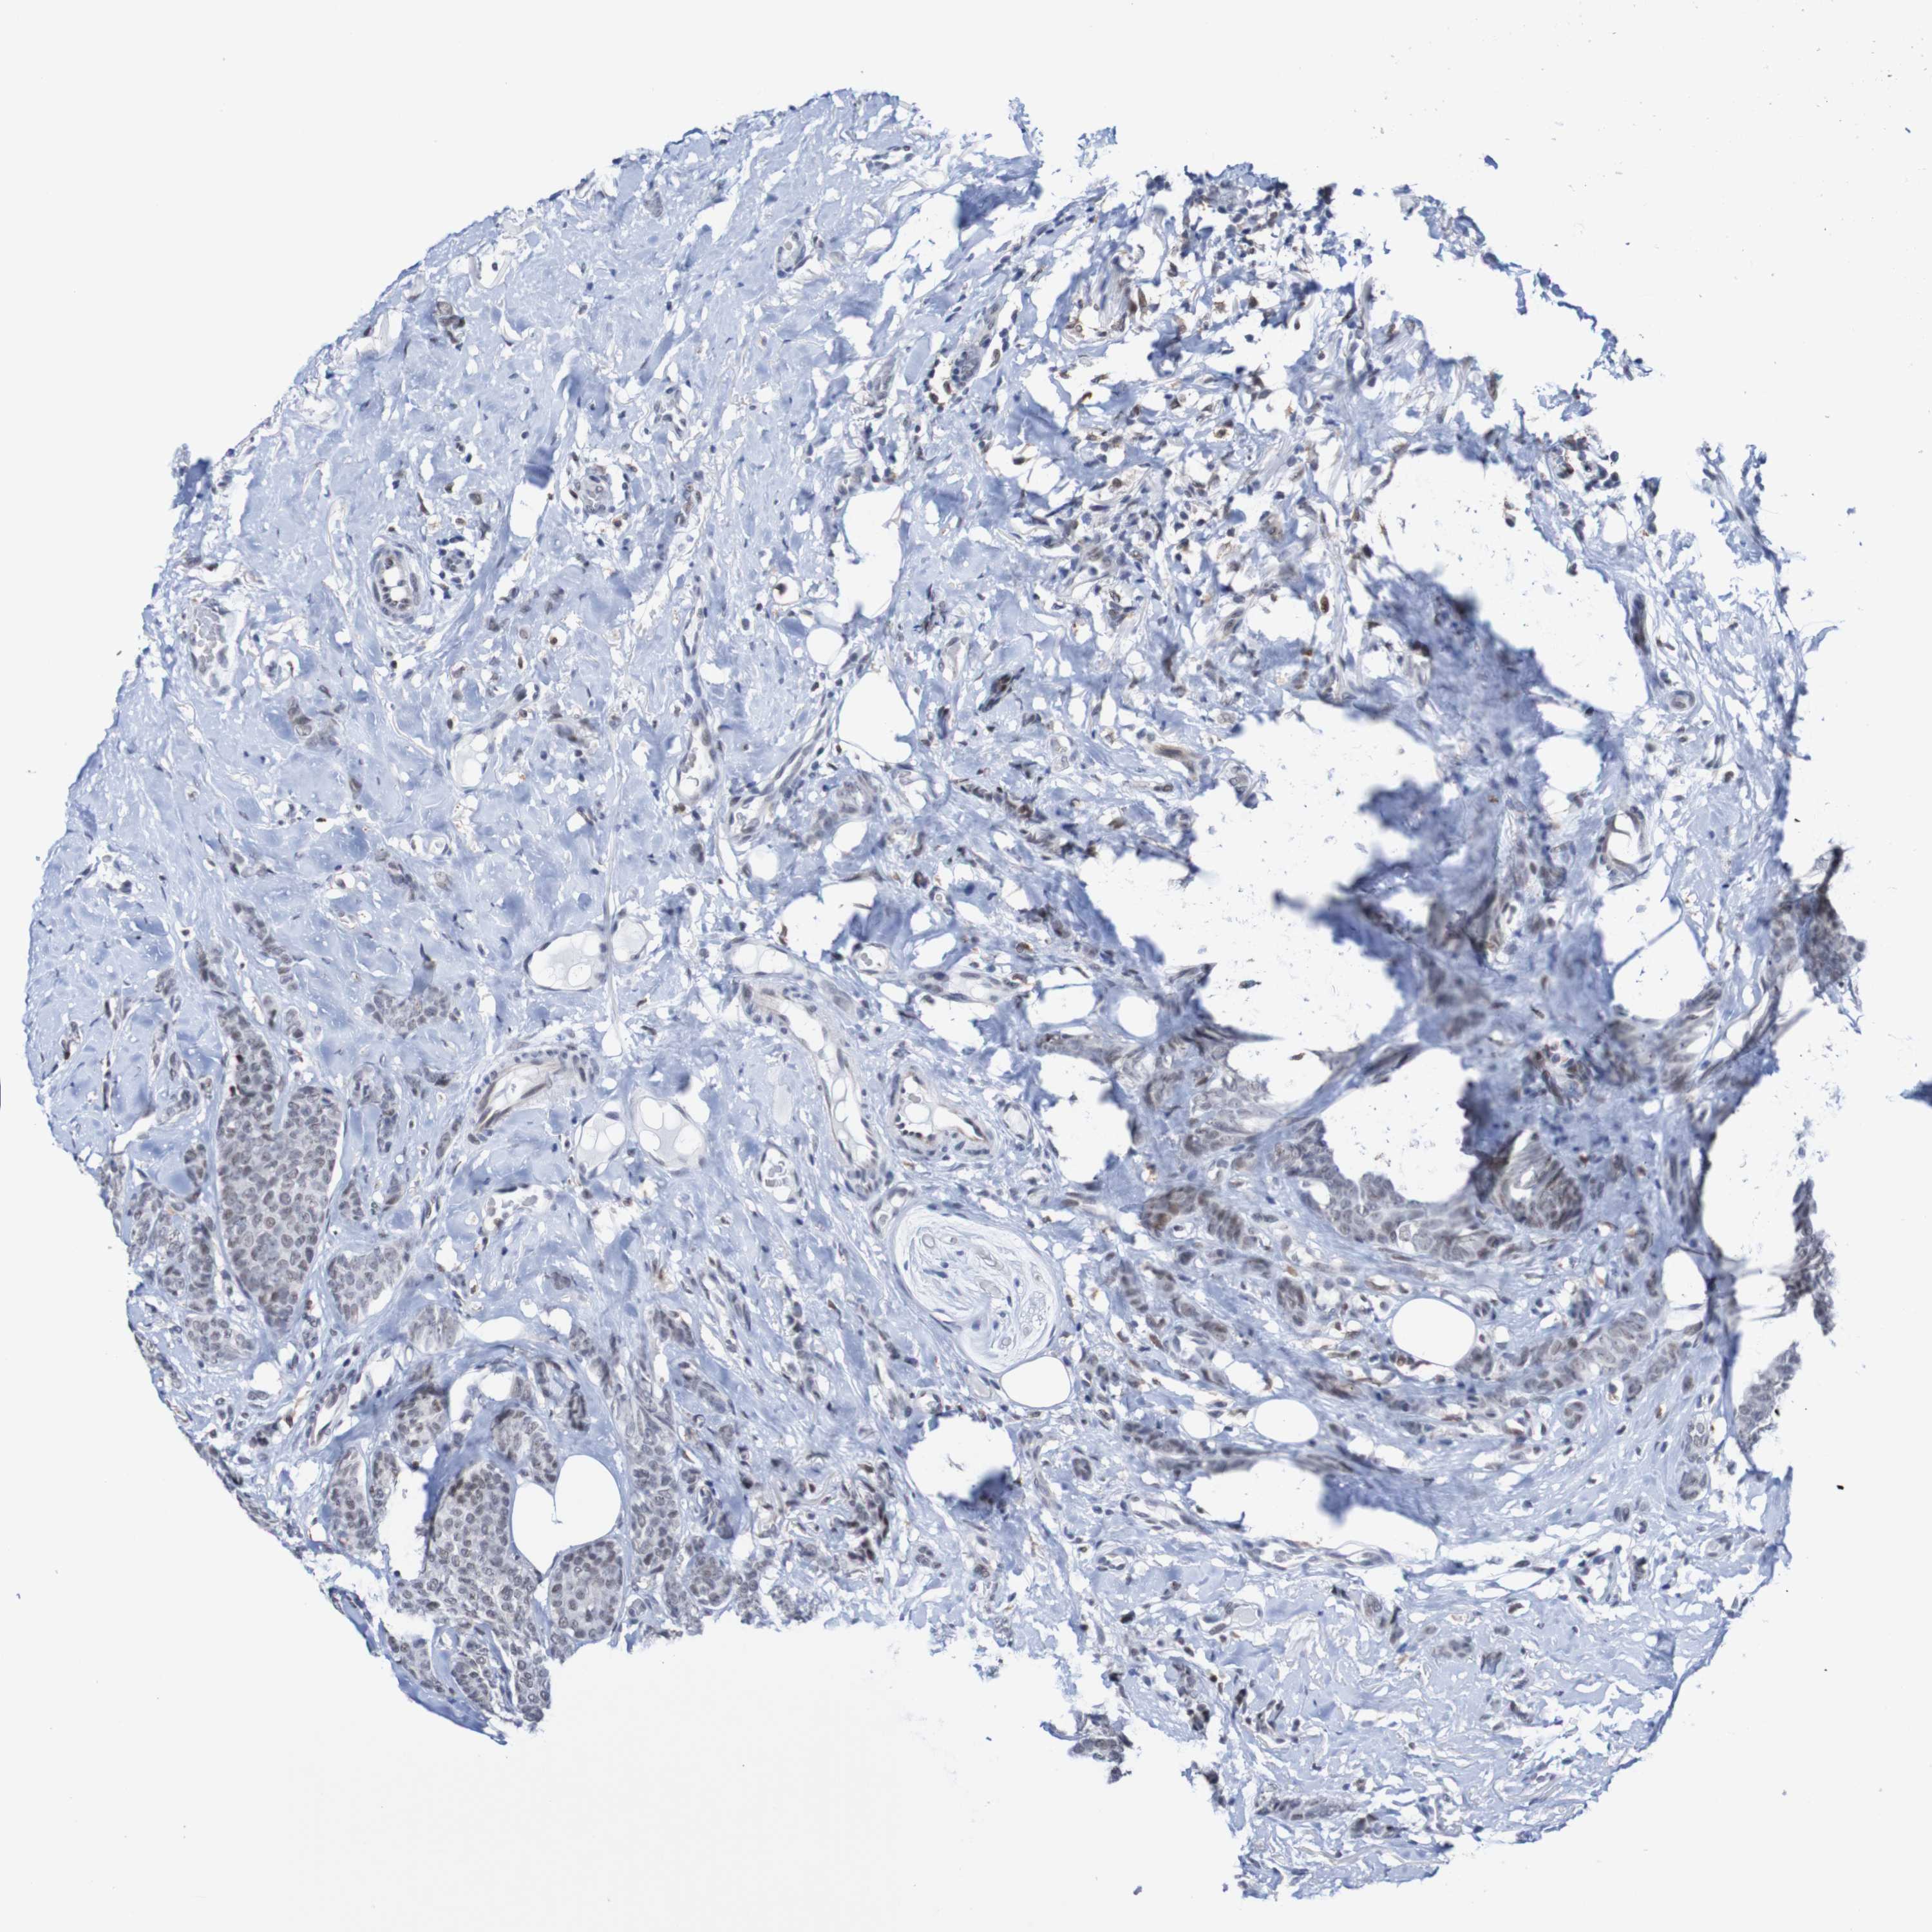

CANCER BREAST CANCER Show tissue menu

BRCA TCGA BRCA VALIDATION PROTEIN EXPRESSION